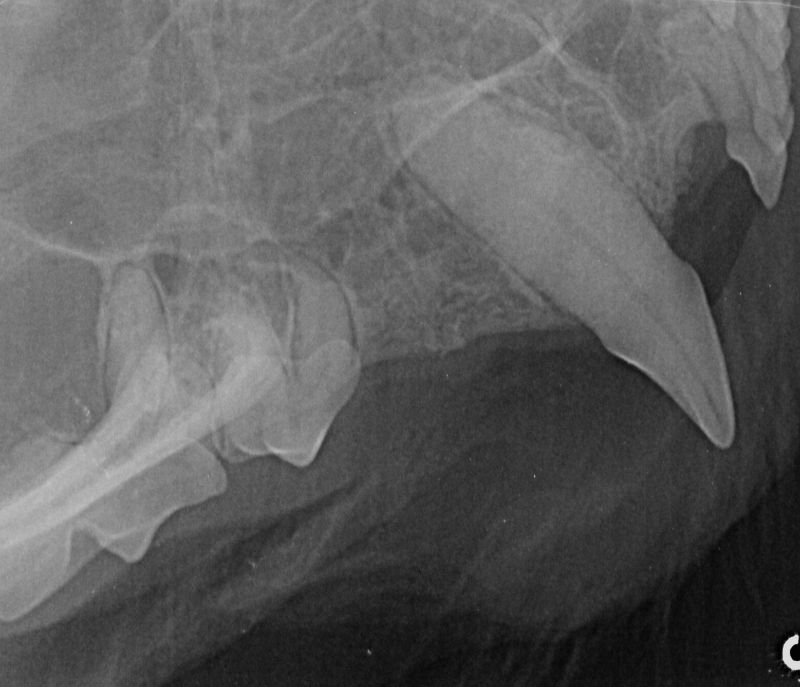

We like to avoid removing teeth where possible, and have a state of the art dental xray so we can check the health of the teeth below the line. This provides us with more information than just the visual appearance, giving us more opportunities to save the teeth!

When we perform dental cleans not only do we deep clean all the teeth on the outside and inside surface, we probe all the teeth looking for pockets that may suggest disease below the gum line. We then polish all the teeth and use a pet friendly mouth wash that results in a gleaming new smile and fresh breath!